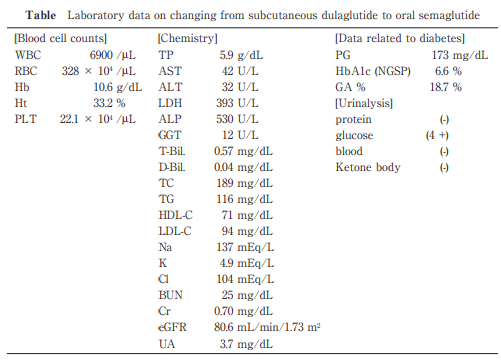

Exacerbation in Glycemic Control by Switching from Subcutaneous Dulaglutide Injection to Oral Semaglutide Administration in a Patient with Type 2 Diabetes, Who Had Undergone Gastrectomy

https://doi.org/10.51040/dkmj.2023-060

Kohzo Takebayashi et al.

Published online : December 26 , 2024